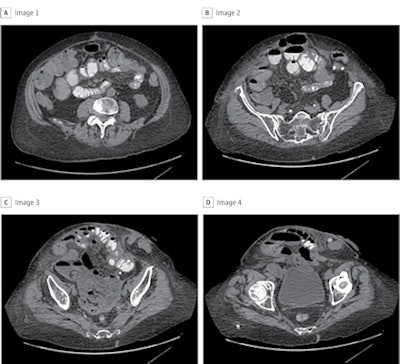

To capture the entire hernia defect for this patient, a total of 22 images were included for the development of the deep-learning model. Panels A through D are four representative CT cuts in order from cranial to caudal. Images and caption courtesy of JAMA Surgery.The surgical complexity deep-learning model validation set showed a receiver operating curve (ROC) of 0.74, and when its performance was compared with surgeons' predictions, it had higher accuracy (81.3% vs. 65%).